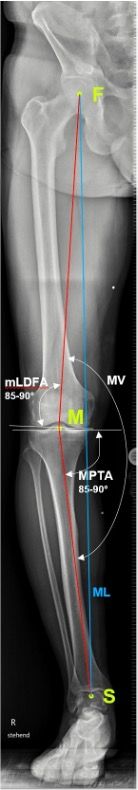

Preoperative deformity analysis in the frontal plane according to Paley [13]

Determination of weight bearing line (Mikulicz line), MPTA (medial proximal tibia angle), mLDFA (mechanical lateral distal femoral angle) and the mechanical varus angle are the 4 key parameters of analysis in the frontal plane (Fig. 1a). The joint line obliquity (JLO) and joint line congruence angle (JLCA) are used as extended parameters for the planning of a double level osteotomy (DLO) in varus deformities on the femur and the tibia as well as the bony correction angle in any varus thrust (Fig. 1b).

Preoperative deformity analysis in the sagittal plane

In the sagittal plane the tibial slope should be measured to exclude any deformity that should be corrected during osteotomy (Fig. 1 C)

Planning the extent of the correction in the frontal plane

The objective of a correction is the shift of the weight bearing line to lateral of the eminence in a tightly defined target range and simultaneous achievement of full knee extension.

Fujisawa [15] defined the ideal correction at around 35% lateral of the eminence for all grades of cartilage lesions (Fig. 1d).

We adjust the extent of the correction or the lateral shift of the weight line to the individual degree of cartilage lesions [14].

Grade 1−2 10−20%

Grade 3 20−25%

Grade 4 30−35%

With a medial open-wedge correction of the tibia, the MPTA angle should be no more than 94° after the correction, because otherwise the joint line obliquity (JLO) is more than plus 4°, which results in clinically relevant shear forces in the joint and to poorer clinical outcomes.

Cases of major correction (>10°) are almost always due to a combined deformity of femur and tibia. If the deformity is mainly on the femur, the correction must be performed at the femur. In around 10−15% of cases no acceptable joint line obliquity (JLO) can be achieved with only one correction on femur or tibia. In these cases a simultaneous double level osteotomy (DLO) correction on the femur (lateral closing wedge) and tibia (medial open wedge) should be performed [16−17].

Planning with calculation of the correction angle was performed according to Miniaci [18] (Fig. 1e). Planning can be performed either manually or using digital software. It is important when planning the bone correction angle that an abnormal joint line convergence angle (JLCA) (see Fig. 1b) is included in the planning (alpha angle minus JLCA >2°) because otherwise the osteotomy will result in an overcorrection to valgus deformity.